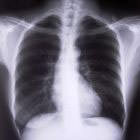

Одно из самых печальных последствий курения – онкологические заболевания. Чаще всего это рак легких. На ранних стадиях рак можно вылечить, но беда в том, что мало кто обращается к врачам, чтобы пройти в целях профилактики полное обследование. Иногда метастазы и раковые опухоли в легких могут быть обнаружены случайно при обращении по поводу другого заболевания. Кстати, на ранней стадии рак легких вообще никак не проявляется, зато имеет тенденцию быстро метастазировать в печень, мозг, кости, почки.

Поэтому, например, в Израиле, кроме активной пропаганды здорового образа жизни, благодаря которой курят в стране менее 20% взрослого населения, врачи рекомендуют курильщикам со стажем регулярно проходить диагностическое обследование на современном оборудовании: позитронно-эмиссионных и компьютерных томографах. Эти аппараты дают изображения с высочайшей резолюцией, и позволяют распознать раковые опухоли в самом начале развития. А бороться с только что появившейся опухолью гораздо легче, чем с опухолью, проросшей в окружающие ткани и сосуды, и буквально уничтожающей легкое изнутри.